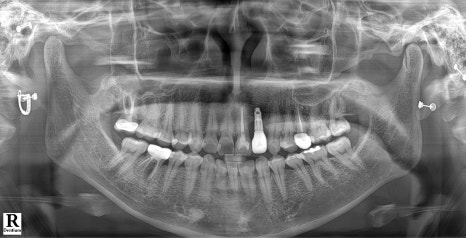

왼쪽 사진: “처음 내원 시 찍은 엑스레이입니다. 앞니 중간에 있는 치아(#22번)는 임플란트가 심어져 있었고, 나머지는 모두 본인의 자연치였습니다.”